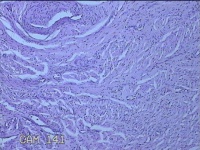

宫颈2点、10点组织

性别

女

年龄

21岁

临床诊断

人乳头瘤病毒感染

一般病史

发现人乳头瘤病毒5个月。

标本名称

大体所见

1.“宫颈2点组织”:灰白粉红色组织0.8x0.5x0.2cm一块。 2.“宫颈10点组织”:灰白暗红色组织0.8x0.6x0.3cm一块。